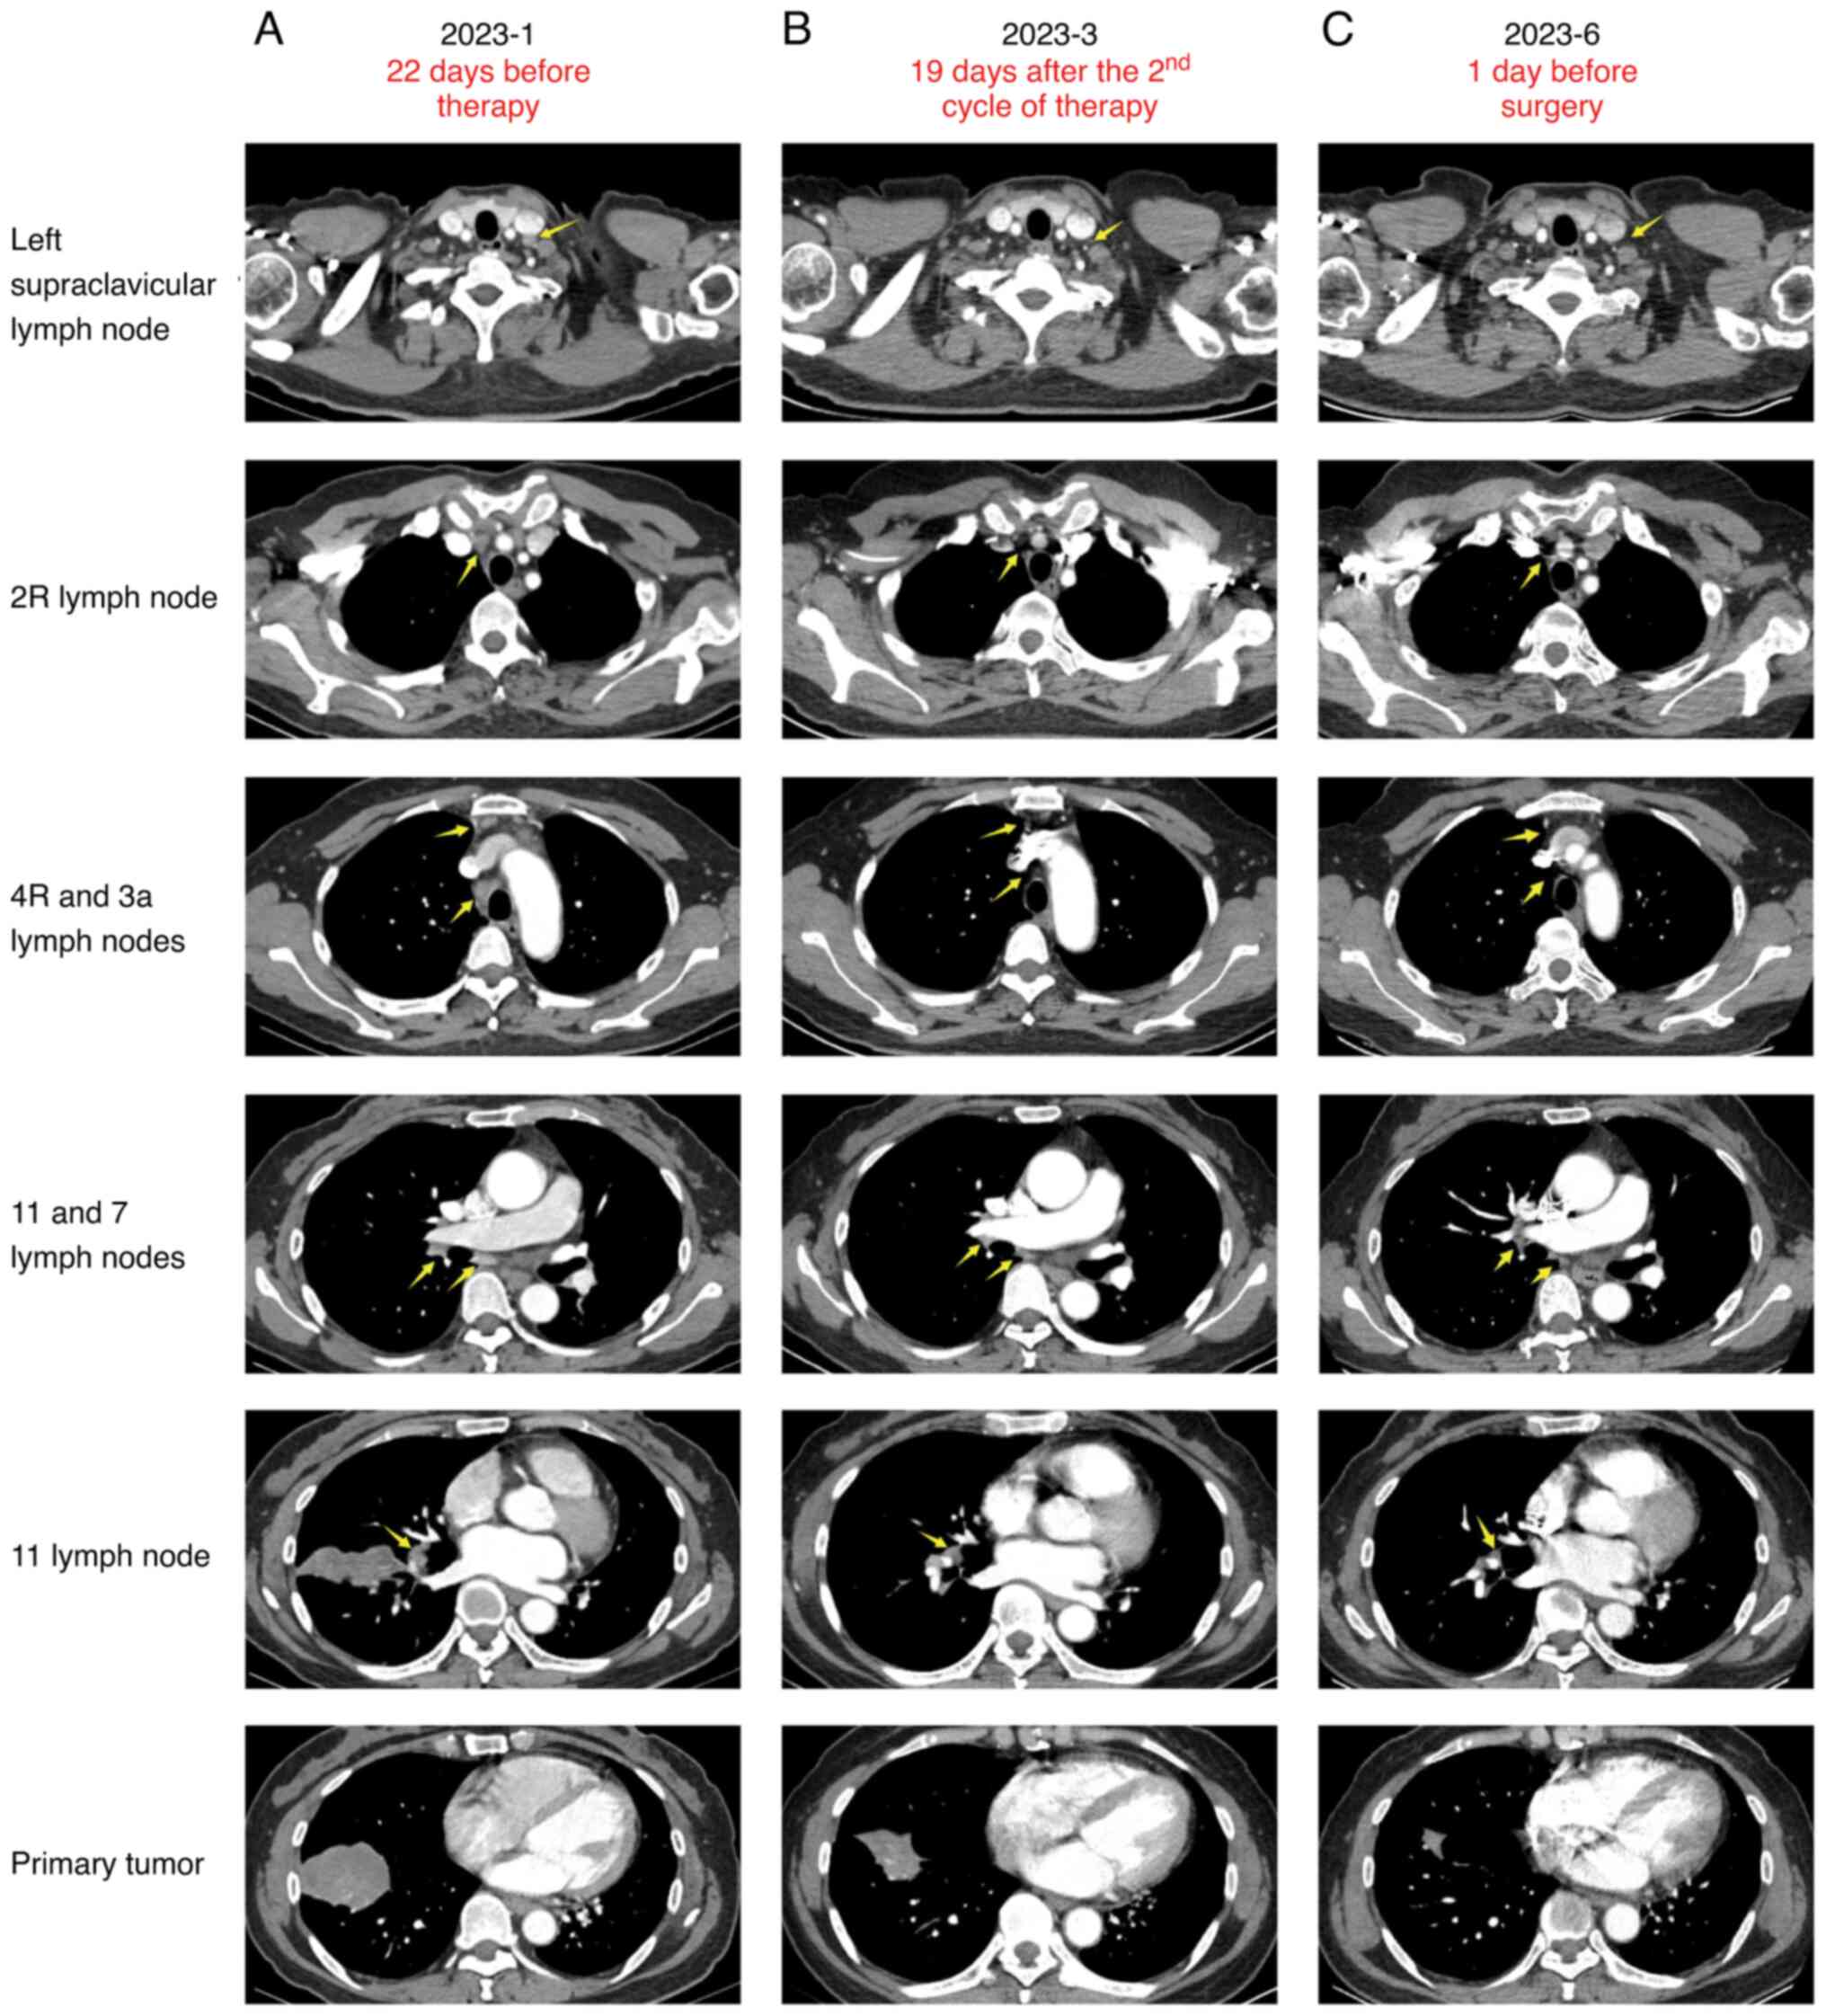

Successful conversion surgery following tislelizumab with chemotherapy in a patient with stage IIIC lung adenocarcinoma harboring RET fusions: A case report and review of the literature

Immune checkpoint inhibitors (ICIs) have emerged as a beacon of hope for most patients with stage III non‑small cell lung cancer (NSCLC) who are no longer surgical candidates. However, the literature on the use of immunotherapy in patients with NSCLC with rearranged during transfection (RET) gene fusions is scant. The present study reports the case of a 61‑year‑old female patient, diagnosed with stage IIIC lung adenocarcinoma, exhibiting two RET gene fusions and high programmed death‑ligand 1 expression. Following four treatment cycles of tislelizumab in combination with pemetrexed and cisplatin, the patient was successfully downstaged, enabling radical surgery. The post‑operative pathology analysis indicated a major pathologic response. This case study contributes to the growing body of evidence supporting the use of ICIs in treating locally advanced NSCLC with RET gene fusions.